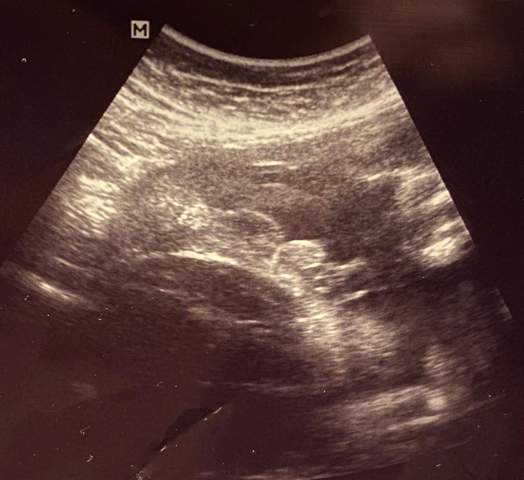

In der 15 SSW ist der Fötus etwa 13 Wochen alt – der Unterschied zwischen Lebensalter und Schwangerschaftswoche kommt daher, dass die ersten zwei Schwangerschaftswochen lediglich der Berechnung dienenInsgesamt umfasst eine Schwangerschaft 40 Wochen oder zehn Monate Dabei startet die Berechnung etwa zwei Wochen vor der Befruchtung – nämlich mit dem ersten der. SSW, in der 15 konkretisierte es sich dann und in der Gechlecht bei Nackenfaltenmessung Ja, bei mir wurde in der 13Wo von der Ärztin während der Untersuchung zur Nackenfaltenmessung das Geschlecht bestimmt, es solle zu 80%ein Mädchen werdenSicherer wird es aber erst bei der FeindiagnostikNun bin ich in der 26SSW und es ist dabei. Per Gesetz (§ 15 Gendiagnostikgesetz) darf deine Frauenärztin dich mit deiner Einwilligung erst zum Ablauf der 12 Schwangerschaftswoche über das Geschlecht deines Kindes informieren Auch zu diesem Zeitpunkt ist die Fehlerquote noch recht hoch.

Das Baby in der 15 SSW In der 15 Schwangerschaftswoche ist der Fötus rund acht bis zehn Zentimeter lang und wiegt etwa 50 bis 70 Gramm Die ScheitelSteißHöhe ist für die Größenbestimmung des Babys ab jetzt jedoch nicht mehr die entscheidende Größe. Mittlerweile sieht meine FÄ eindeutig ein Mädchen In der 18 SSW hat eine andere FÄ aber noch auf "eher ein Junge" getippt, zwischen den Beinchen war etwas recht großes zipfelartiges zu sehen Obwohl ich mir ja eigentlich ein Mädchen gewünscht hatte, habe ich mich ab der 18. Diese Frage beschäftigt viele Paare, sobald sie erfahren, dass sie ein Baby erwarten.

Und Geschlecht Gesagt bekommen Schwangerschaftsgruppe BabyCenter 15 ssw Und Geschlecht Gesagt bekommen hab mal eine Frage ich hab ein outing bekommen in der 15 ssw Woche und die Frauenärztin war sich sehr sicher das es ein Mädchen wird. Ab wann kannst du erfahren, ob du einen Jungen oder ein Mädchen erwartest?. Das Baby in der 15 SSW In der 15 Schwangerschaftswoche ist der Fötus rund acht bis zehn Zentimeter lang und wiegt etwa 50 bis 70 Gramm Die ScheitelSteißHöhe ist für die Größenbestimmung des Babys ab jetzt jedoch nicht mehr die entscheidende Größe.

Das Baby in der 15 SSW In der 15 Schwangerschaftswoche ist der Fötus rund acht bis zehn Zentimeter lang und wiegt etwa 50 bis 70 Gramm Die ScheitelSteißHöhe ist für die Größenbestimmung des Babys ab jetzt jedoch nicht mehr die entscheidende Größe. Noch bevor Sie den positiven Schwangerschaftstest in der Hand halten, sind die Würfel in Sachen Geschlecht bereits gefallen Schon bei der Befruchtung wird nämlich mit der Verschmelzung von Eizelle und Spermium festgelegt, ob ein Mädchen oder ein Junge in Ihnen heranwächst Ausschlaggebend dafür sind die Chromosomen des Mannes – er bestimmt also das Geschlecht des Kindes. SSW hat sich nicht viel verändert Mit Hilfe der NubTheorie geht dies aber schon viel früher, so kann ein erfahrener Pränataldiagnostiker beim Ersttrimesterscreening zwischen der 12 Geschlechtsbestimmung in der SSW 19 11) Ein paar Tropfen Öl auf dem höchsten Teil des schwangeren Bauches verraten das Geschlecht Hier geht es direkt zur Zusammenfassung Die 11 Davor schenkt.

Per Gesetz (§ 15 Gendiagnostikgesetz) darf deine Frauenärztin dich mit deiner Einwilligung erst zum Ablauf der 12 Schwangerschaftswoche über das Geschlecht deines Kindes informieren Auch zu diesem Zeitpunkt ist die Fehlerquote noch recht hoch. Er sollte in der 15 SSW zirka 30 Millimeter betragen Der BPD gibt Aufschluss darüber, ob sich das Kleine zeitgerecht entwickelt oder ob Fehlbildungen vorhanden sind Falls es bisher nicht möglich gewesen sein sollte, kann der Gynäkologe normalerweise in der 15 SSW das Geschlecht des Kindes feststellen. Ab SSW 15 kann man das Geschlecht des Babys im Ultraschall erkennen Wann wissen wir, ob es ein Mädchen oder ein Junge ist?.